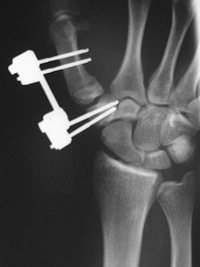

Die oben aufrufbaren Seiten zeigen Beispiele verschiedener Operationsverfahren. Es wurden Beispiele gewählt, die mögliche Stabilisierungen von Frakturen vorschlagen, wie sie oft im Bereich der Traumatologie vorkommen.

Alle gezeigten Verfahren haben folgenden Grundsatz:

1. Weichteilschonend

2. Stabil aber dynamisch

3. Minimal invasiv

4. Bei Infektrisiko (offene Frakturen, Weichteilquetschung) immer erst den Fixateur externe und dann Verfahrenswechsel zum Verriegelungnagel.

5. Ausheilung wenn möglich und vom Patienten akzeptiert auch im Fixateur.

6. Am Unterschenkel ist bei offenen Frakturen der Fixateur die erste Wahl, am Oberschenkel in der Regel der Verriegelungsnagel.

7. Bei primärer Versorgung der Tibiafraktur mit dem Fixateur, sollte zu einem späteren Zeitpunkt der Verfahrenswechsel zum Verriegelungsnagel erwogen werden. der Verfahrenswechsel sollte innerhalb von 14 Tagen erfolgen. Zum späteren Zeitpunkt ist der Verfahrenswechsel risikoreicher.